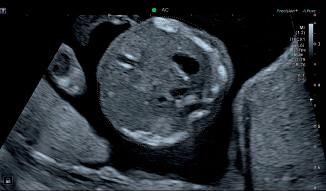

Figure 1: Non-contrast brain CT demonstrating a small amount of subarachnoidal hemorrhage in the central sulcus on the right side. Figure 2: Head CTA demonstrating a short segment occlusion of a middle cerebral artery branch on the left side. Figure 3: Brain CT perfusion of the patient in Figure 2 demonstrating a perfusion deficit in the left hemisphere with a pattern of infarct core with surrounding penumbra. Left: Dr. Ruud Becks, Radiologist, Radboudumc. Right: Dr. Anton Meijer, Neuroradiologist, Radboudumc.